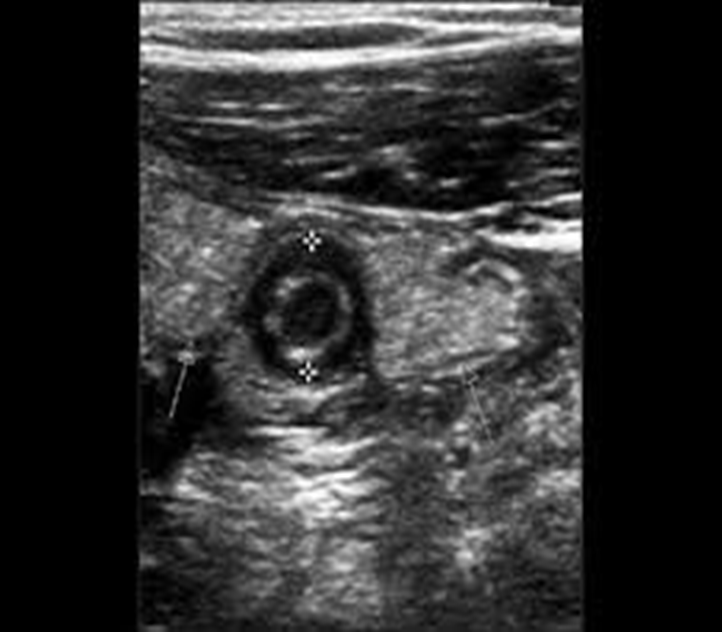

Ghi nhận hình ảnh trên siêu âm:

Cấu trúc hình ống đầu tận d= 8mm  nằm ở vùng bụng dưới bên phải ấn không xẹp ,thành ruột thừa  dày và phù nề hình bia bắn mô mỡ xung quanh ruột thừa tăng âm (tăng sáng) do phản ứng viêm.

Hình ảnh viêm túi thừa manh tràng : hình ảnh rải rác vài túi thừa tại manh tràng cấu trúc hình túi,mô mỡ thâm nhiễm dày, phản ứng viêm xung quanh;